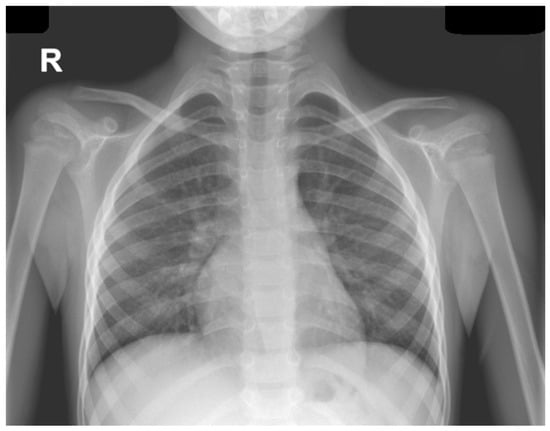

Background: Durvalumab, a PD-L1 inhibitor used as consolidation therapy after chemoradiation in unresectable stage III non–small cell lung cancer (NSCLC), can induce immune-related adverse events, among which immune-mediated pneumonitis represents one of the most severe. Differentiating checkpoint inhibitor pneumonitis (CIP) from infectious pneumonia is challenging due to overlapping clinical and radiologic findings. Case presentation: We describe a 67-year-old woman with stage III lung adenocarcinoma treated with chemotherapy, radiotherapy, and durvalumab, who presented with progressive dyspnea and extensive bilateral ground-glass opacities on CT imaging. Laboratory tests revealed leukopenia and elevated inflammatory markers. Despite broad-spectrum antibiotic and antiviral therapy, her condition worsened, requiring high-flow nasal cannula oxygen therapy. Multiplex molecular testing on sputum identified human metapneumovirus (HMPV), while blood cultures and urinary antigens for Streptococcus pneumoniae and Legionella pneumophila were negative. A pulmonology consultation raised suspicion for severe durvalumab-induced pneumonitis exacerbated by viral infection. High-dose methylprednisolone (2 mg/kg/day) followed by a four-week taper led to gradual clinical and radiologic resolution. Durvalumab was permanently discontinued. Discussion: To our knowledge, this is the first reported case of HMPV-associated pneumonitis in a patient receiving durvalumab. This case highlights the potential synergistic interplay between viral infection and immune checkpoint blockade, resulting in severe lung injury. Comprehensive microbiologic evaluation, including molecular diagnostics, is essential to guide therapy and distinguish infectious from immune-mediated causes. Conclusions: Early recognition of mixed infectious and immune-mediated pneumonitis, and timely corticosteroid therapy are critical to achieving favorable outcomes and preventing irreversible pulmonary damage. Full article

Figure 1